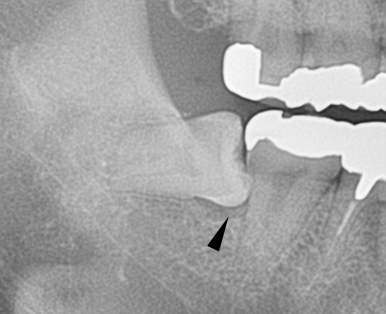

同じ症例をレントゲン写真で見たところです。親知らずが横倒しに生えていて、周りの骨を溶かしてしまっています。

親知らずが横(水平)に生えている写真です。隣の歯との隙間は歯磨きすることは出来ません。放っておくと、次の写真の様になります。

左の親知らずは、大事な一本前の歯を虫歯にし、さらに周りの骨を溶かしています。こうなってからでは遅すぎてしまいます。